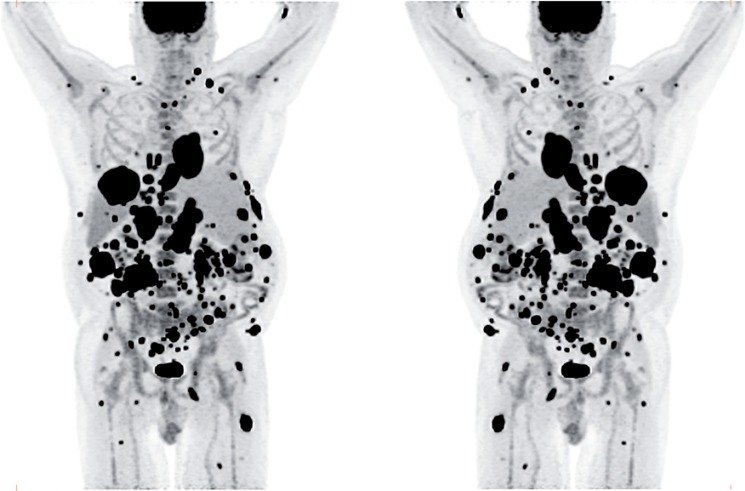

The patient was referred for 18F-FDG-PET/CT the next day to further evaluate the disease extent. A whole-body PET/CT was performed 60 min after the intravenous injection of 629 MBq (17 mCi) 18F-FDG. The study showed multiple hypermetabolic foci throughout the body (Figure 1). There was a large soft tissue mass in the right lower lobe with increased 18F-FDG uptake; the maximum standardized uptake value (SUVmax) of this lesion was 38.0. Also, there were multiple hypermetabolic nodules in the thyroid, gastric mucosa, pancreas, and both the adrenals. Both kidneys contained exophytic lesions with increased 18F-FDG uptake (Figure 2). A circumferential soft tissue mass in the esophagus was hypermetabolic as well. Additional FDG-avid nodules and masses were also found in the peritoneum and omentum; the largest of these had a SUVmax of 68.0. Intense FDG uptake was observed in multiple subcutaneous and intramuscular nodules throughout the body, some of which were thought to represent lymph nodes. Brain magnetic resonance imaging was performed on the same day, which revealed five metastatic lesions measuring up to 1.5 cm in the left frontal lobe, anterior right parietal lobe, and right temporal lobe. At this point, there were multiple candidate lesions for the primary malignancy, such as lung, esophagus, melanoma, or an aggressive lymphoma.

Figure 1.

Maximum intensity projection (MIP) images in anterior and posterior views of the 18F-FDG PET/CT images showing multiple hypermetabolic foci of increased FDG uptake throughout the body, most likely representing widespread metastatic disease.